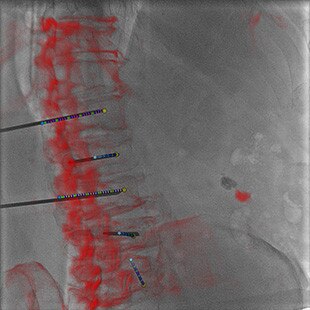

Guider